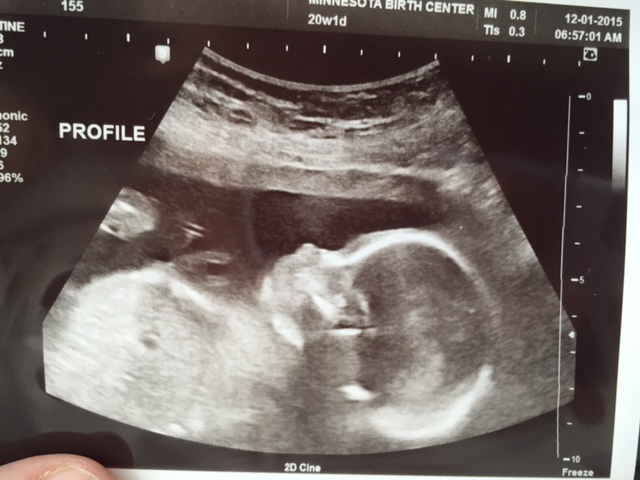

UPDATE!!! It's a girl -- confirmed at 20wks!!! Can't really believe it quite yet. So happy!!!! DS1 is thrilled to have a little sister (did not want another bro, lol). DS2 doesn't want either a lil sis or bro. Ha.

Attachment 28762 Attachment 28763